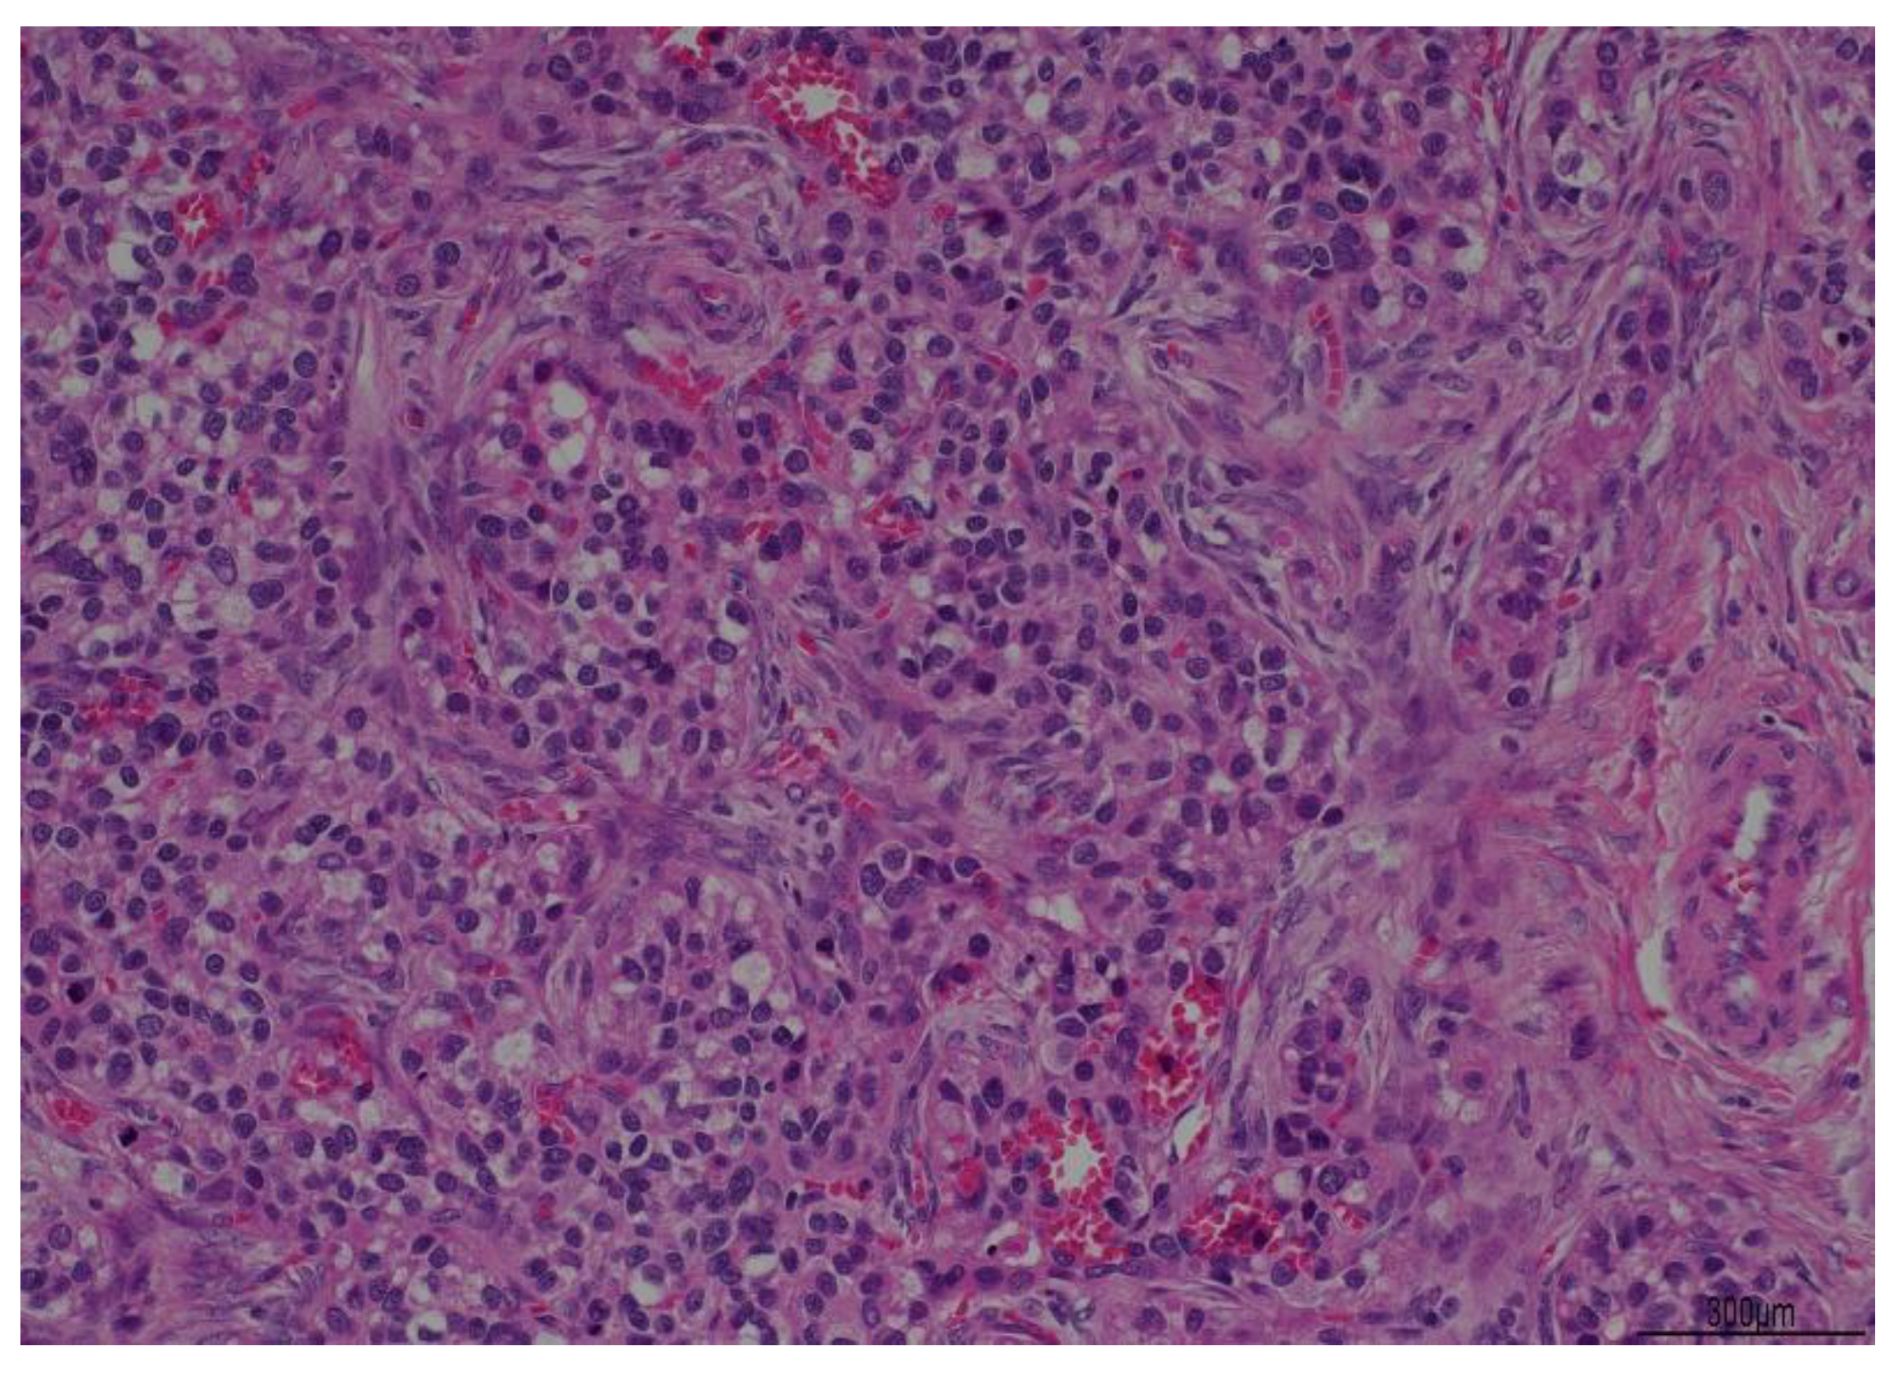

A Rare Case of Hepatocellular Carcinoma Recurrence in Ovarian Site after 12 Years Mimicking a Hepatoid Adenocarcinoma: Case Report

2. Case Report